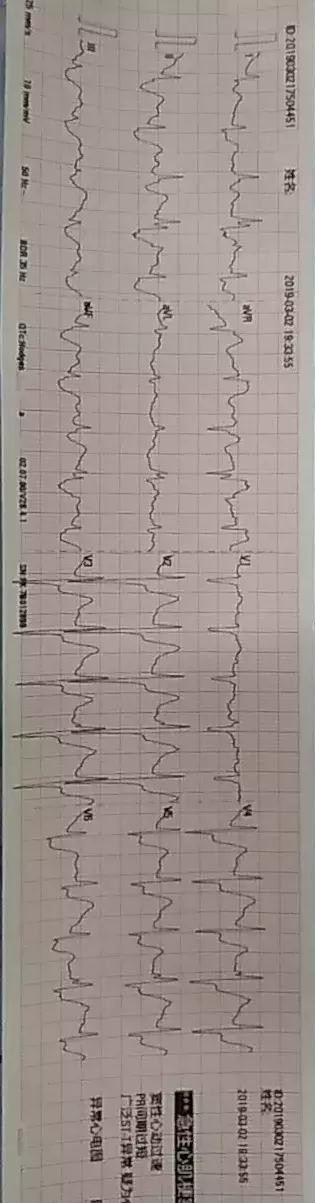

急性左主干心肌梗死的心电图表现多种多样,不同时间点上采集到的心电图也会大不相同:可以表现为前壁和其它导联ST段的抬高,可以表现为前壁导联的de winter样改变,可以表现为多数导联的ST段压低,可以表现为AVR导联的ST段抬高,还可以表现为各种快速性的心律失常。

上)外院的一份心电图:窦性心动过速,除AVR外多个导联的ST段明显压低,为心肌严重缺血缺氧心电图,见于大块的肺动脉栓塞、左主干急性闭塞和/或冠状动脉多支血管病变。

上)冠状动脉造影证实是左主干急性闭塞,术前心电图表现见上图。